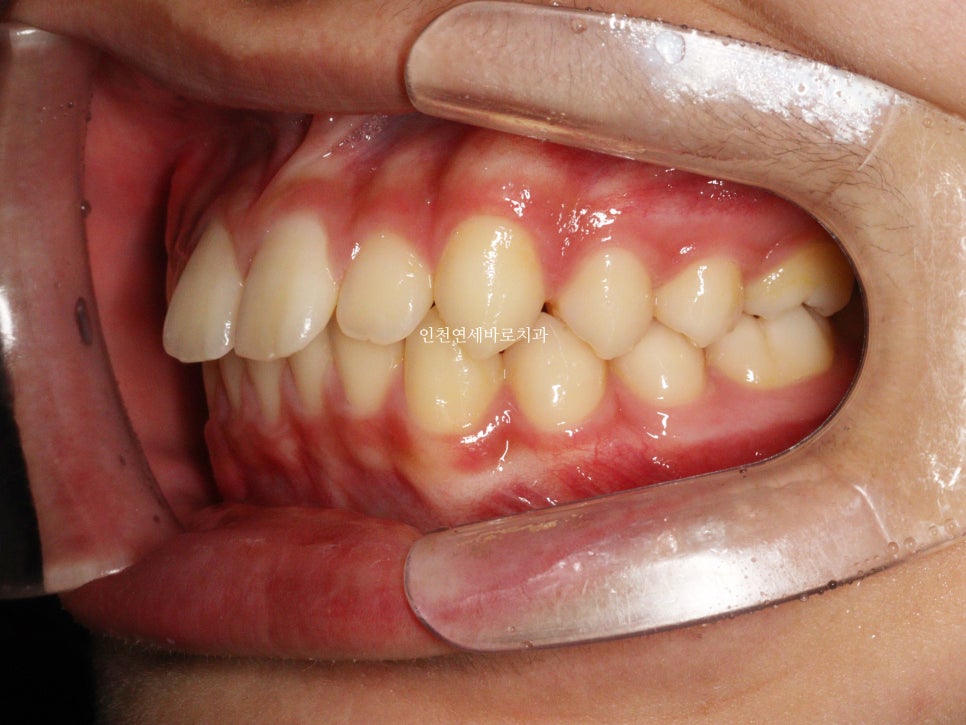

치료 전과 후 입니다.

앞니가 후방이동 한것이 확인됩니다.

우리는 부분교정을 한것이 아니라 간단한 전체교정을 한것입니다.

전과 후의 얼굴 변화입니다.

치아가 들어가보입니다.

앞니만 철사를 붙여서는 얻기 어려운 결과라고 생각합니다.